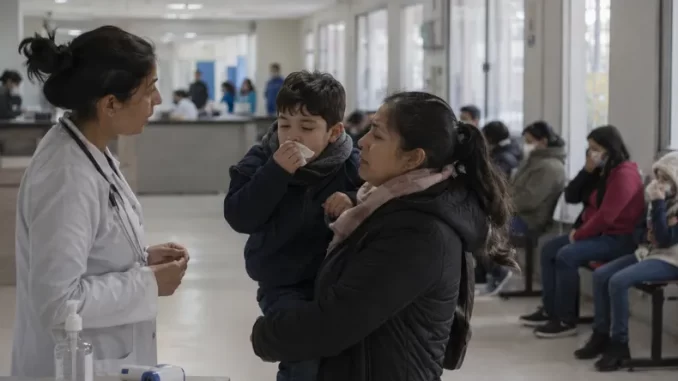

Salud distribuyó más de 550 mil dosis adicionales de vacuna antigripal para adultos

El Ministerio de Salud de la Nación distribuyó 553.948 dosis adicionales de la vacuna antigripal para adultos en respuesta al pedido de refuerzo realizado por las jurisdicciones y, mediante este nuevo envío, se [Mas Info]